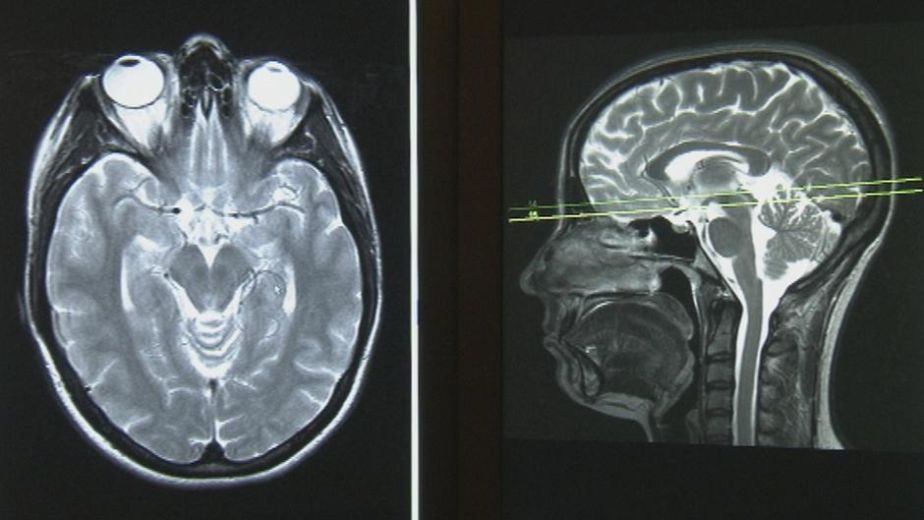

توضيح معنى أشعة الدوبلر أو Doppler Ultrasound بشكل مبسط ، هي عبارة عن نوع من أنواع الموجات فوق الصوتية الحديثة ، بينما يكتفي السونار التقليدي بإظهار صورة للجنين وأعضائه، يقوم فحص الدوبلر بقياس سرعة واتجاه تدفق الدم داخل الشرايين والأوردة، وبالاخص تلك المرتبطة بـ المشيمة والحبل السري للطفل ، و باستخدام تقنية الدوبلر، يسهل من دور الطبيب فى تشخيص دقيق للحالة وإذا ما كان الجنين يحصل على الغذاء والأكسجين بشكل كافى أم لا، وبالتالي من الممكن التنبؤ بأي أعراض قد تؤثر على نموه وصحته في المراحل القادمة ومحاولة تجنبها .

الفرق بين الدوبلر والسونار

السونار: يعرض صورة للجنين، توضح شكله ووضعيته وبعض تفاصيل الأعضاء.

الدوبلر: يحتوي تقريباً على مميزات السونار مع اضافة ميزة قياس تدفق الدم وتحديد اتجاهاته، وهو ما يساعد الطبيب على تقييم حالة المشيمة والحبل السري بشكل دقيق .

وهنا يتضح الفارق وهو أن السونار يرى الأعضاء، أما الدوبلر فيرى حركة الدم داخلها.